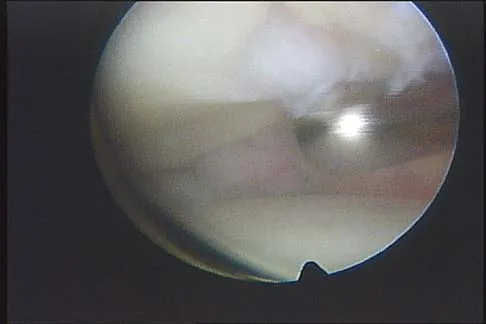

Question 100

A 16-year-old girl has a painful foot mass. A radiograph, MRI scan, and biopsy specimens are shown in Figures 35a through 35d. What is the most likely diagnosis?

Explanation